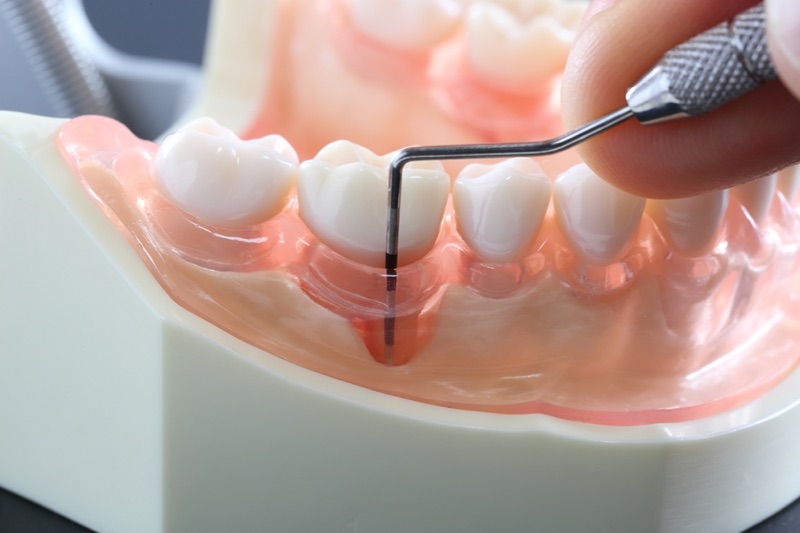

当院の歯周病治療の特徴

歯科用CTを使った正確な診断

歯周病は進行すると骨が溶けてしまう病気ですが、 2次元パノラマの歯科用レントゲンでは骨の厚みや密度まで確認することはできません。

当院で導入している歯科用CTは3次元画像で診断が出来るため、歯や顎の骨の状況を立体的に把握でき、歯周病の進行度を正確に診断することができます。

レーザーで痛みの少ない治療を実現

当院では、症状に合わせて「CO2レーザー(炭酸ガスレーザー)」を使った歯周病治療を行っています。CO2レーザーには殺菌作用や止血作用があり、治療時の腫れや出血を抑えることができます。レーザーを患部に照射するだけで、刺激や温度の上昇による痛みはほとんどなく、体への負担の少ない治療が可能になります。